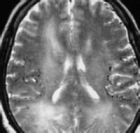

腦卒中分為缺血性和出血性兩大類,由血管阻塞引起缺血性腦中風又稱腦梗塞,占中風的70%-80%。在腦血管病猝死事件中,腦梗塞占80%。突然發生腦梗塞,會使患者致死、致殘,大多數家屬覺得這是不可避免的意外。但是專家認為,腦梗塞病人大多有腦血管狹窄的基礎病變,如果能提前通過超聲或血管造影發現腦血管狹窄,及時疏通血管,就能預防突發腦梗塞。

臨床表現以猝然昏撲、不省人事或突然發生口眼歪斜、半身不遂、舌強言蹇、智力障礙為主要特徵。腦中風包括缺血性中風(短暫性腦缺血發作、動脈粥樣硬化性血栓性腦梗塞、腔隙性腦梗塞、腦栓塞)、出血性中風(腦出血、蛛網膜下腔出血)、高血壓腦病和血管性痴呆四大類。